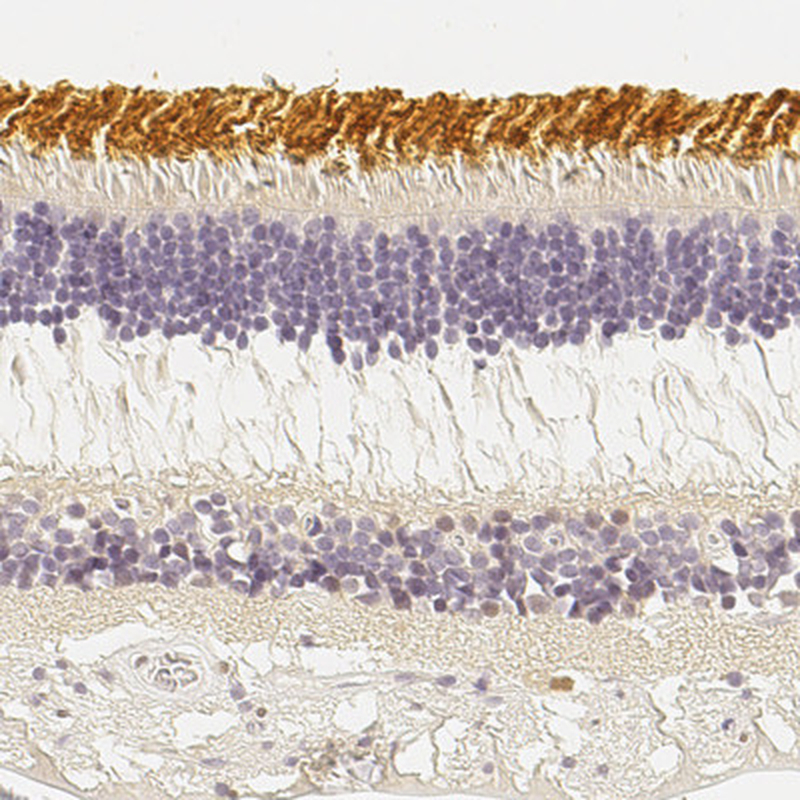

Immunohistochemical staining of human eye, retina, kidney, liver and lymphoid tissues using Anti-OPN1SW antibody HPA014083 (A) shows similar protein distribution across tissues to independent antibody HPA013562 (B).